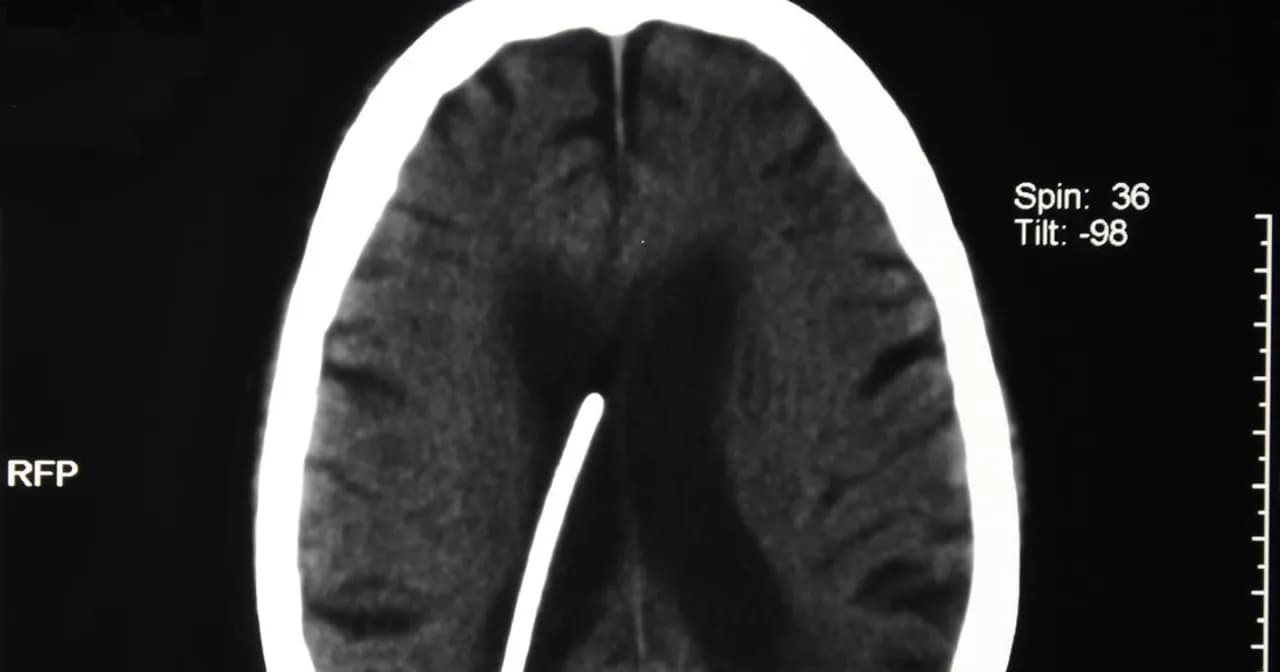

Rozpoznanie wodogłowia u dorosłych opiera się na różnych metodach diagnostycznych. Lekarze często zaczynają od szczegółowego wywiadu medycznego, aby zrozumieć objawy pacjenta. Następnie mogą zlecić badania obrazowe, takie jak rezonans magnetyczny (MRI) lub tomografia komputerowa (CT), które pozwalają ocenić stan mózgu i obecność płynu mózgowo-rdzeniowego.

Oprócz badań obrazowych, lekarze mogą również przeprowadzać testy neurologiczne, aby ocenić funkcje mózgu oraz koordynację ruchową pacjenta. Wczesne diagnozowanie jest kluczowe, aby rozpocząć odpowiednie leczenie i zminimalizować ryzyko powikłań zdrowotnych.